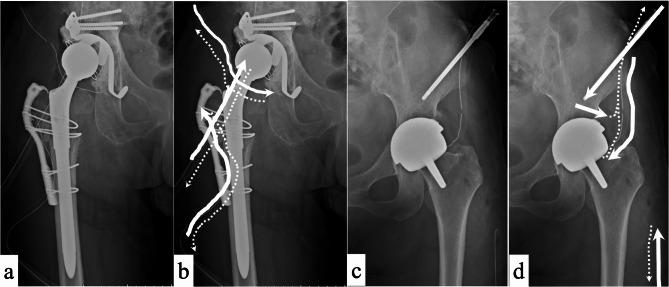

Periprosthetic joint infection (PJI) is a complication of peri-implant biofilm-based treatments and confers resistance to antimicrobial therapy. Integrating continuous local antibiotic perfusion (CLAP) with conventional surgery for PJI facilitates the local delivery of low-flow, high-concentration antimicrobials. This study aimed to evaluate the efficacy and safety of CLAP for treating PJI. This study included patients diagnosed with hip PJI who underwent debridement, antibiotics, and implant retention (DAIR) augmented by CLAP. Gentamicin was administered at a high concentration (1.2 mg/mL) and low flow rate (2.0 mL/h for 24 h). We evaluated implant survival and complication rates associated with adding CLAP to conventional DAIR surgery. Of the 22 patients, including 11 with chronic infection, DAIR surgery supplemented with CLAP resulted in implant survival in 20 patients (90.9%). In contrast, among 10 patients treated with DAIR without CLAP (non-CLAP group), implant survival was 70%. The mean follow-up period was 42.6 ± 31.5 (range, 12-161) months in the CLAP group and 56.8 ± 28.8 (range, 28-114) months in the non-CLAP group. During CLAP treatment, renal function worsened in two patients; however, it improved rapidly after CLAP completion and device removal. No major complications were observed. CLAP demonstrated promising results in treating acute and chronic PJI. However, monitoring and regulating blood antimicrobial levels is crucial to avoiding renal dysfunction. CLAP is a treatment option for PJI that can destroy bacterial biofilms.

人工关节周围感染(PJI)是基于种植体周围生物膜治疗的一种并发症,对抗菌治疗具有耐药性。将持续局部抗生素灌注(CLAP)与PJI的传统手术相结合,有助于低流量、高浓度抗菌药物的局部递送。本研究旨在评估CLAP治疗PJI的疗效和安全性。本研究纳入了诊断为髋关节PJI并接受清创、抗生素治疗和保留植入物(DAIR)并辅以CLAP的患者。庆大霉素以高浓度(1.2mg/mL)和低流速(2.0mL/h,持续24小时)给药。我们评估了在传统DAIR手术中添加CLAP后的植入物存活率和并发症发生率。22例患者中,包括11例慢性感染患者,DAIR手术辅以CLAP后,20例患者(90.9%)的植入物存活。相比之下,在10例接受无CLAP的DAIR治疗的患者(非CLAP组)中,植入物存活率为70%。CLAP组的平均随访期为42.6±31.5(范围12 - 161)个月,非CLAP组为56.8±28.8(范围28 - 114)个月。在CLAP治疗期间,两名患者的肾功能恶化;然而,在CLAP完成和取出装置后迅速改善。未观察到重大并发症。CLAP在治疗急性和慢性PJI方面显示出有前景的结果。然而,监测和调节血液抗菌水平对于避免肾功能障碍至关重要。CLAP是一种可破坏细菌生物膜的PJI治疗选择。